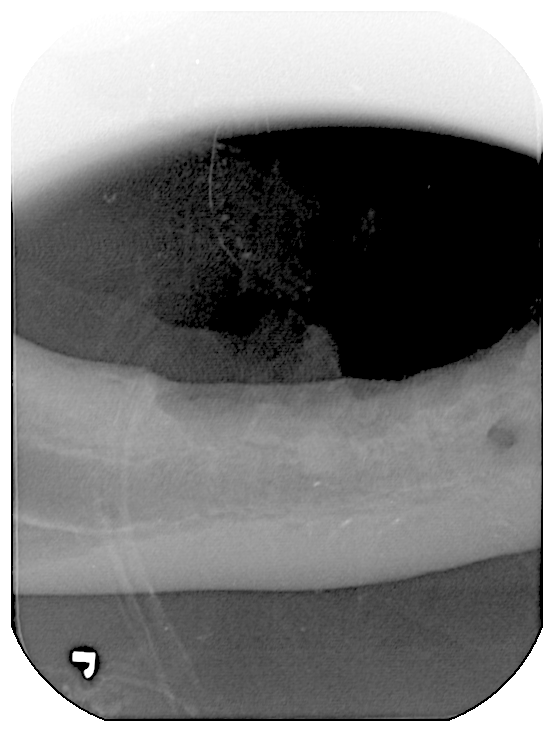

치료중 대상묘

![]() ![]()